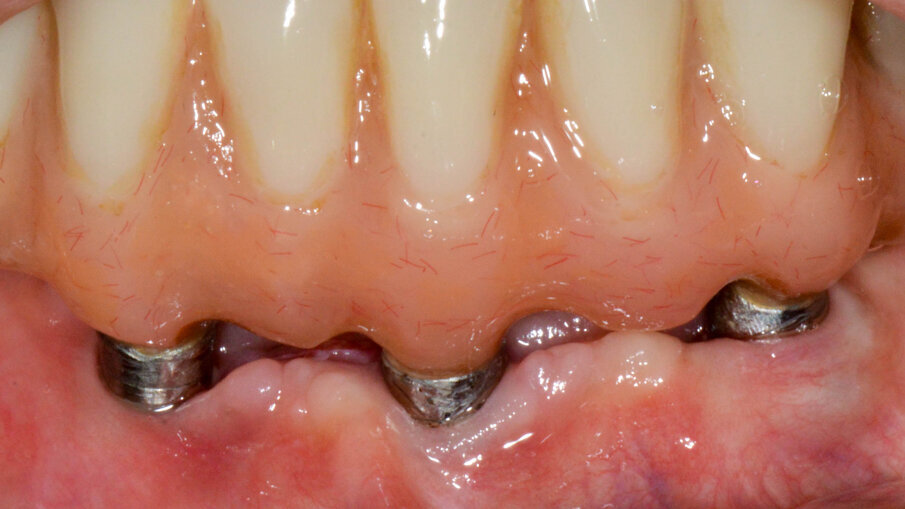

Figure 2a-c. Pre-operative clinical photographs.

Clinical examination revealed 5 implants in the mandible supporting a fixed full arch reconstruction. Probing pocket depths were of the order of 8-9mm around 3 of the anterior implants. The distal implants had normal probing depths. CBCT imaging revealed an intrabony component of 6.1mm for the implant in the 43 position, 4.2mm at the 41 implant and 3.1 at the 33 implant.

A prepatory phase was carried out, including assessment of oral hygiene and non-surgical implant decontamination in 1 session. After 6 weeks, the patient underwent surgical treatment. This comprised of full thickness mucoperiosteal flaps being raised and the chronic inflammatory tissue removed from the defects around the 3 implants with the use of teflon curettes. The implant surface was then decontaminated using EMS AIR-FLOW® technology with very fine erythritol powder (EMS AIR-FLOW® PLUS Powder). The implants were also irrigated and cleansed with saline-soaked cotton foam.